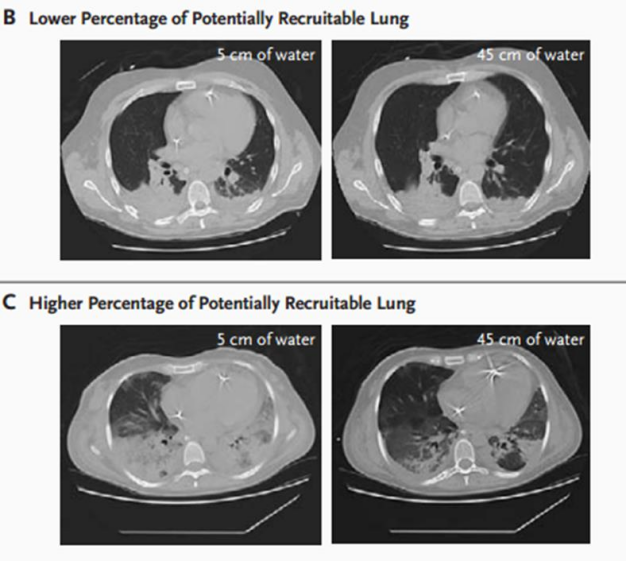

ARDS患者肺的可复张性差异比较大,在肺的不同区域,病变不同。对于高可复张性患者,积极进行肺泡复张能够改善肺泡塌陷,进而改善分流;对于低可复张性患者,肺复张加重肺泡过度膨胀,胸腔内压升高,加重了循环功能恶化。所以,我们要了解肺可复张性,以达到个体化精准治疗;同时避免盲目进行操作造成肺损伤和循环抑制,在实施肺复张时,应明确其适应证和禁忌证,如果患者肺损伤严重,可能出现气压伤,不建议做肺复张。此外,可以优化肺复张及PEEP设置,改善氧合。下图B可以看到,当给患者的压力由5 cmH2O增加到45 cmH2O以后,双下肺实变并没有明显改善,从影像学可以判断该患者的可复张性比较低。下图C可以看到,压力由5 cmH2O增加到45 cmH2O以后,双下肺实变和渗出明显减少,所以该患者可复张性较好。